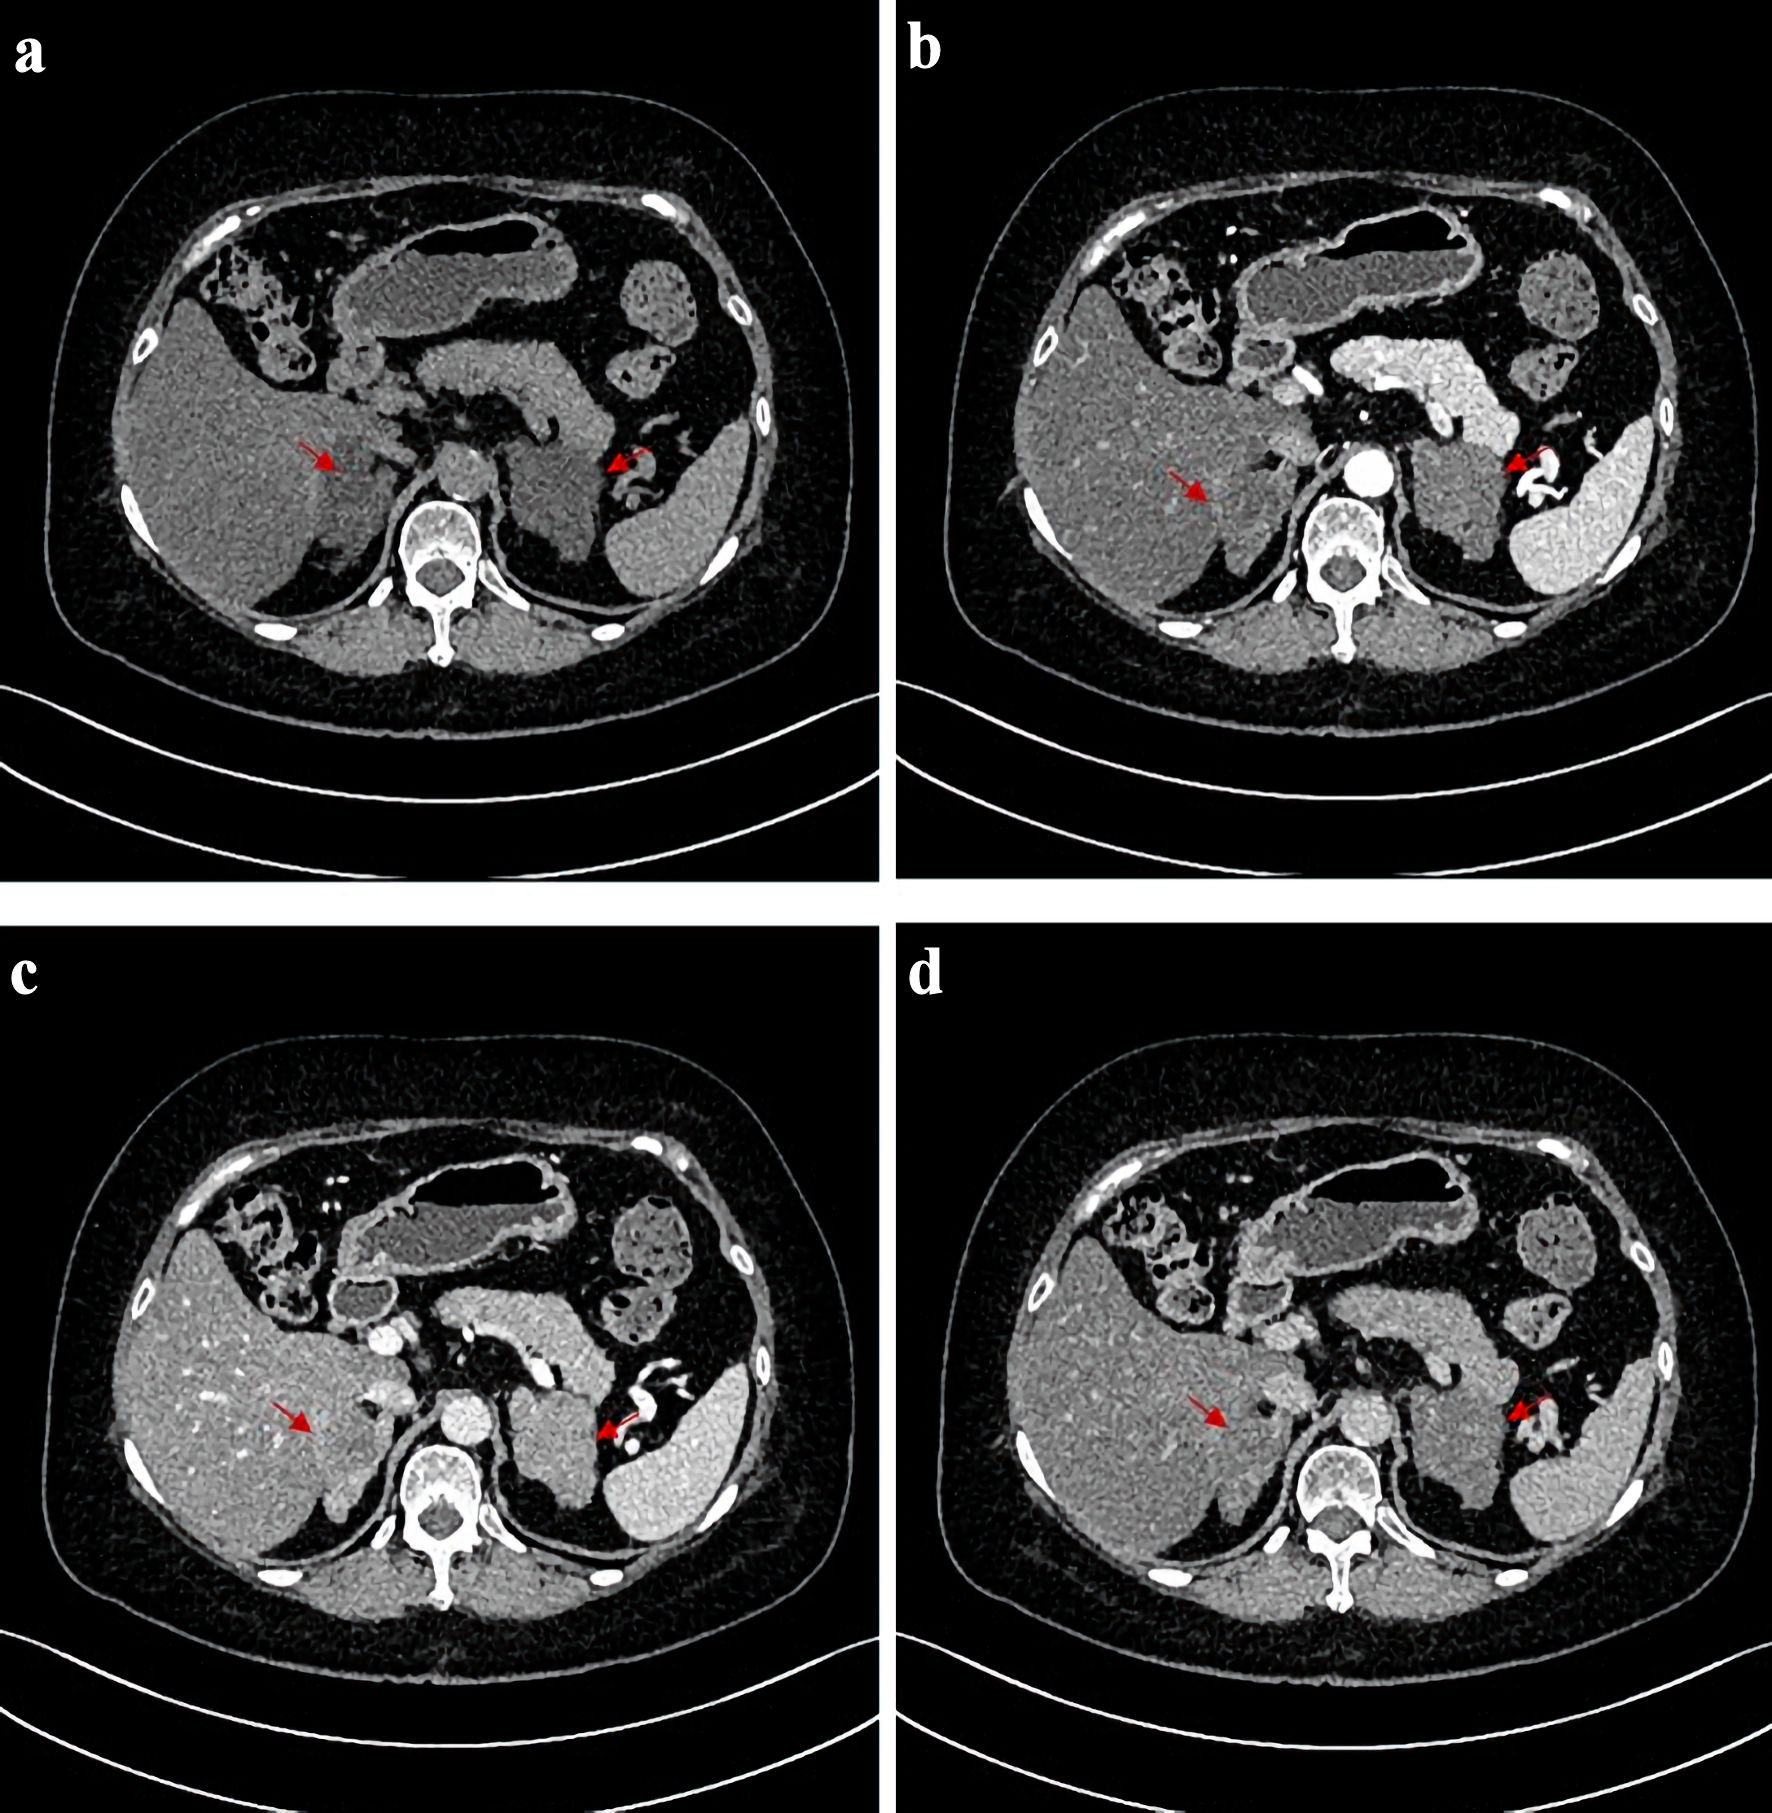

Clinical features

Figure 1. CT scans before operation. CT images of the patient before adrenalectomy. (a) Image of plain CT scan. (b) Image of arterial phase of contrast-enhanced CT. (c) Image of venous phase of contrast-enhanced CT. (d) Image of delayed phase of contrast-enhanced CT. The red arrows point to the position corresponding to bilateral adrenal nodules on both sides. CT: computed tomography.